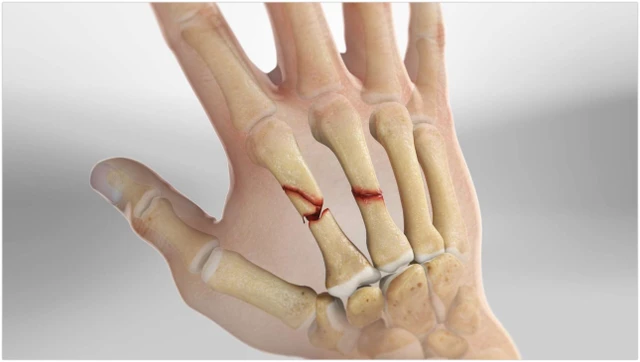

:format(webp)/ran_xuong_tay_bao_lau_thi_khoi_0_401cf54c3c.jpg)

Khi gặp phải tình trạng rạn xương tay, nhiều người thường lo lắng không biết rạn xương tay bao lâu thì khỏi và hồi phục hoàn toàn. Mặc dù không nghiêm trọng bằng gãy xương hoàn toàn, nhưng vẫn cần được chăm sóc đúng cách và có thời gian nghỉ ngơi hợp lý để bảo đảm xương liền lại mạnh mẽ.